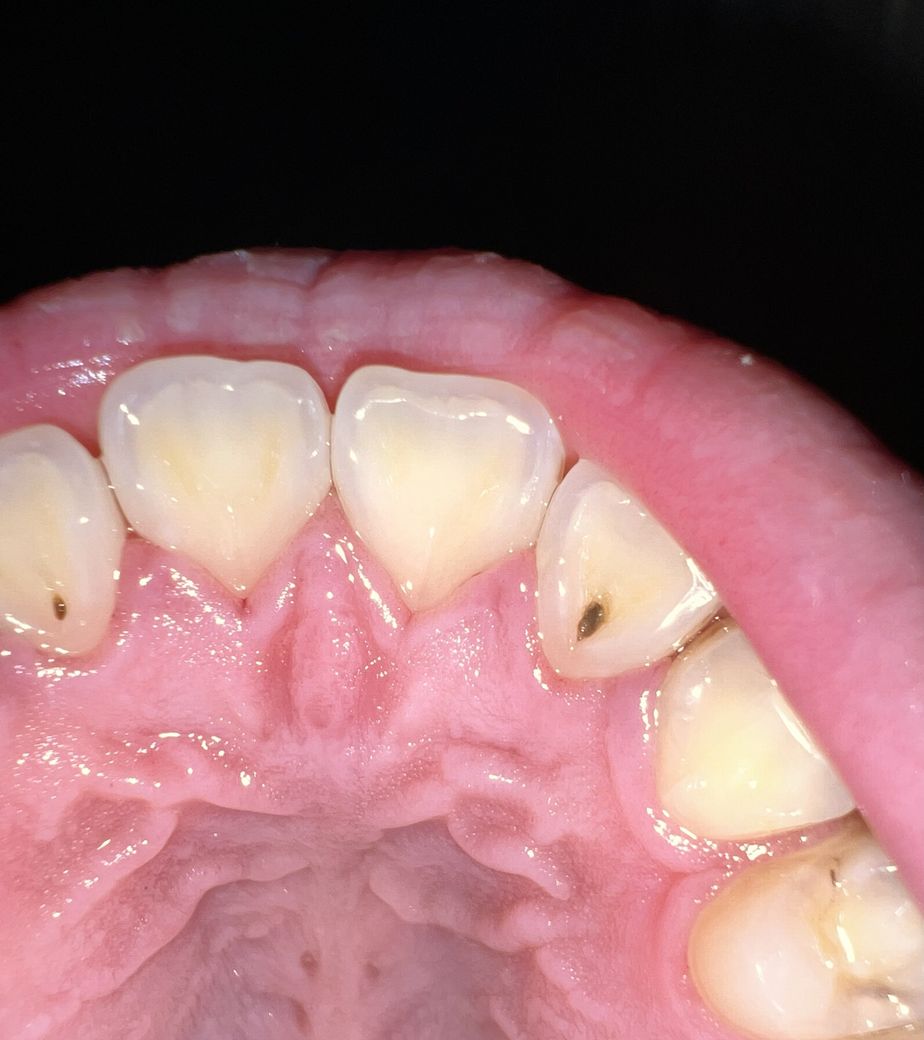

혹시 충치 맞나요? 레진으로 치료 가능한가요? 충지가 몇개 정도 될까요? 비용은 어떻게 되나요? 하루 만에 치료 다 가능할까요?

충치는 3개로 보입니다. 두번째 앞니와 송곳니사이 인접면도 충치가 의심되나 침이 고여있어 정확하게 보이지 않습니다.

치료방법은 의사의 판단에 따라 차이가 있으므로 말씀드리기 어렵지만 레진치료 가능해 보입니다. 레진치료는 하루에 다 끝납니다. 그러나 소구치에 생긴 충치는 인접면까지 진행되었다면 인레이 치료가 필요할 수 있습니다. 측절치 충치는 신경과 근접하게 진행되어 있을 수 있으므로 가까운 시일내에 치과에 내원하셔서 검진 받아 치료하시길 바랍니다.

양쪽 측절치 구개측으로 충치가 보이고 있습니다. 사진에 보이는 4번 치아에도 인접면으로 충치가 의심이 됩니다.

충치가 맞는것 같습니다. 가운데 앞니 옆에 각각한개씩 ㅏ보이고 좌측 송곳니 옆 치아 (작은어금니)에도 초기 충치 있는데 그녀석은 지켜봐도 될것으로 보입니다. 앞니 안쪽 우식은 물론 치근단 사진을 찍어봐야하지만 간단한 레진수복으로 가능할것으로 판단됩니다.

사진으로 보았을때는 양쪽 끝 치아와 가운데치아 이렇게 3개정도 충치가 있는걸로 보이며,

육안으로 보이는 것만 3개 정도 된다고 보시면 됩니다. 다만 해당 치아에 물기가 있어 이를 제거한다면 초기 충치도 있을 수 있습니다.

일단 육안으로 보았을 때 충치 크기가 커 신경치료를 동반해야할 가능성이 매우 높아 보입니다. 하지만 현재 사진으로는 정확한 진단을 할 수 없어 어떤 치료를 할지 그리고 비용은 얼마가 들지에 대해서는 알 수가 없습니다.

측절치에 충치2개가 있고, 송곳니 뒤쪽에도 치아사이 충치가 있습니다.

레진, 또한 인레이 치료가 필요할 수 있습니다. 인레이를 하게되면 2번 내원해야합니다.

사진상으로만 봐서는 충치 3개로 보입니다.